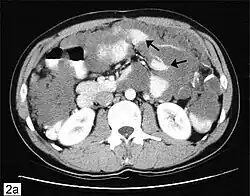

| Computed tomographic scan of an abdomen showing pseudomyxoma peritonei with multiple peritoneal masses (arrow) with "scalloping effect" seen | |